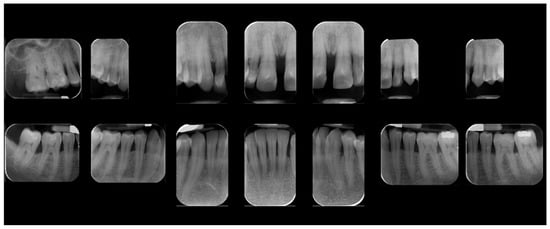

A 39-year-old male patient presented for prosthetic rehabilitation of the anterior maxillary region, primarily motivated by aesthetic concerns and periodontal health improvement. The patient reported a history of smoking (10–15 cigarettes per day since he was 18 years old) and had been diagnosed with localised stage III, grade B periodontitis. Even if the defect is mostly horizontal and localised to the II sextant, stage III was defined due to the bone loss extending to the middle third of the roots and the probing depth is ≥6 mm in this sextant. Moreover, smoking represents a risk factor able to classify the case as grade B. Initial clinical and radiographic evaluation (Figure 1) revealed the absence of all four third molars, the presence of conservative restorations on teeth 1.6, 3.7, and 4.6, and evidence of horizontal alveolar bone resorption in the regions corresponding to teeth 1.4 and 2.3. A conoid morphology was noted in the upper left lateral incisor.

Figure 1. Initial radiographic assessment.